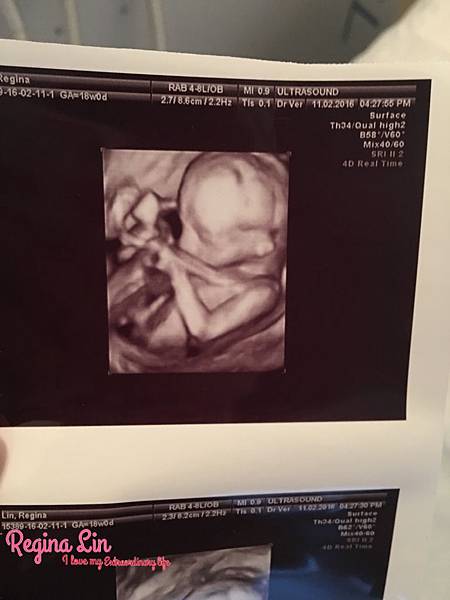

孕期進入第16週、也就是四個月!時間真的用飛的,一下子寶寶就滿四個月。不過吉娜這時候的肚子還算平平的,不講別人可能以為我只是吃飽後有小腹XD 如果你跟吉娜一樣~一開始肚子很平,不要擔心喔、很正常啦!每個人狀況不一樣,有人跟我一樣前期肚子很平、但有人可能一開始就肚子隆起(雖然我懷疑這是吃太多?哈哈哈)其實我甚至覺得前面三四個月基本上不要胖太多,因為後面體重會暴衝(像是我就是)。Regina Lin 發表在 痞客邦 留言(8) 人氣(8,822)